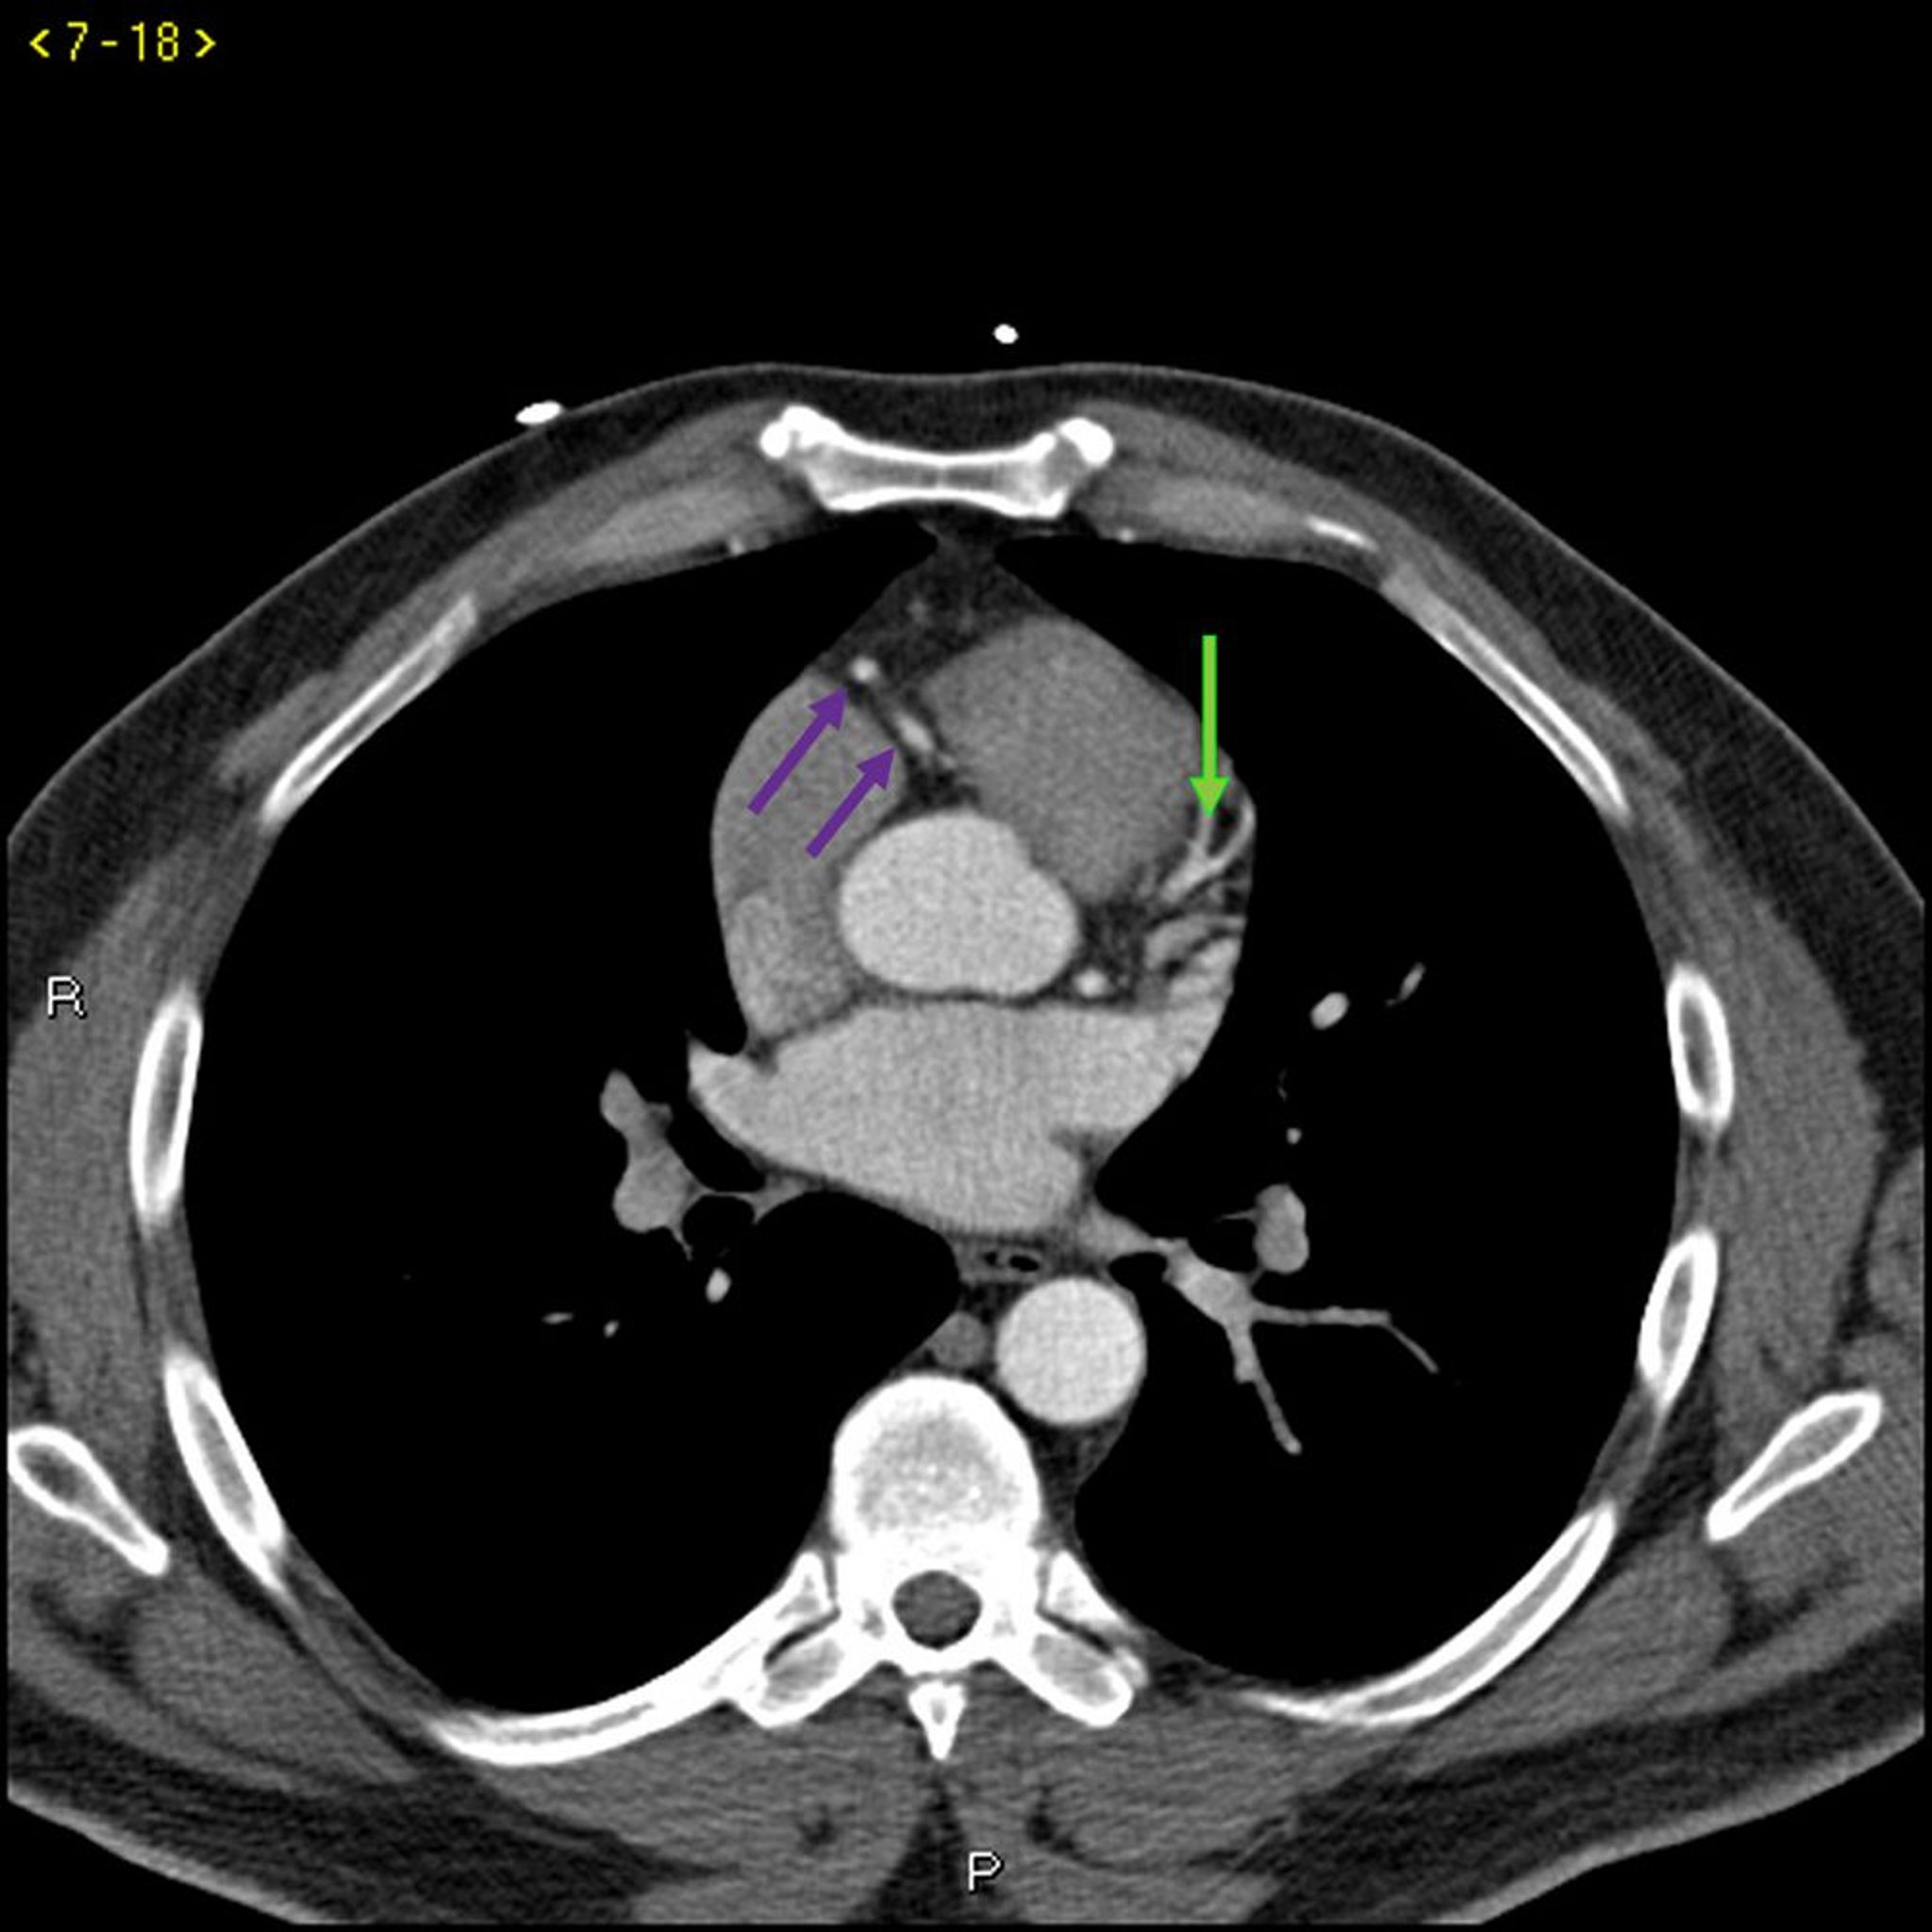

Phim chụp CT có thuốc cản quang cho thấy các động mạch vành bình thường – Lát cắt 3

Phim chụp CT có thuốc cản quang này cho thấy các động mạch vành bình thường. Động mạch chính bên trái được biểu thị bằng mũi tên màu đỏ. Động mạch vành xuống trước trái và động mạch mũ trái lần lượt được biểu thị bằng mũi tên xanh lá cây và xanh lam và động mạch vành phải được biểu thị bằng mũi tên màu tím.